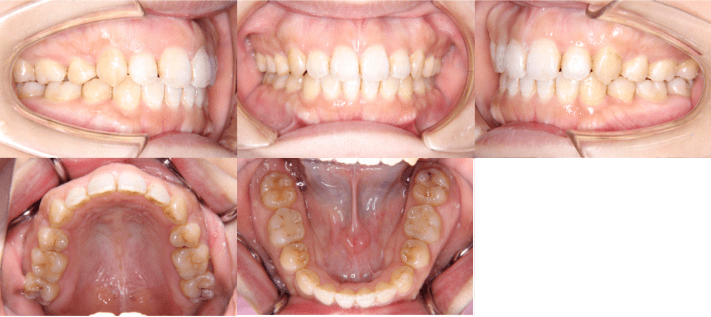

治療後

• 初診時年齢:28歳4ヶ月

• 主訴:前歯のかみ合わせ

• 診断:開咬

• 抜歯箇所:上下左右4

• 治療内容:小臼歯4本を抜歯した後に、マウスピース型カスタムメイド矯正歯科装置(製品名インビザライン 完成物薬機法対象外)を使用して主訴である開咬の改善を行いました。

• 治療期間:2年

• リスク:矯正治療による歯の移動に伴う痛み、歯根吸収、虫歯

• 費用:80万円